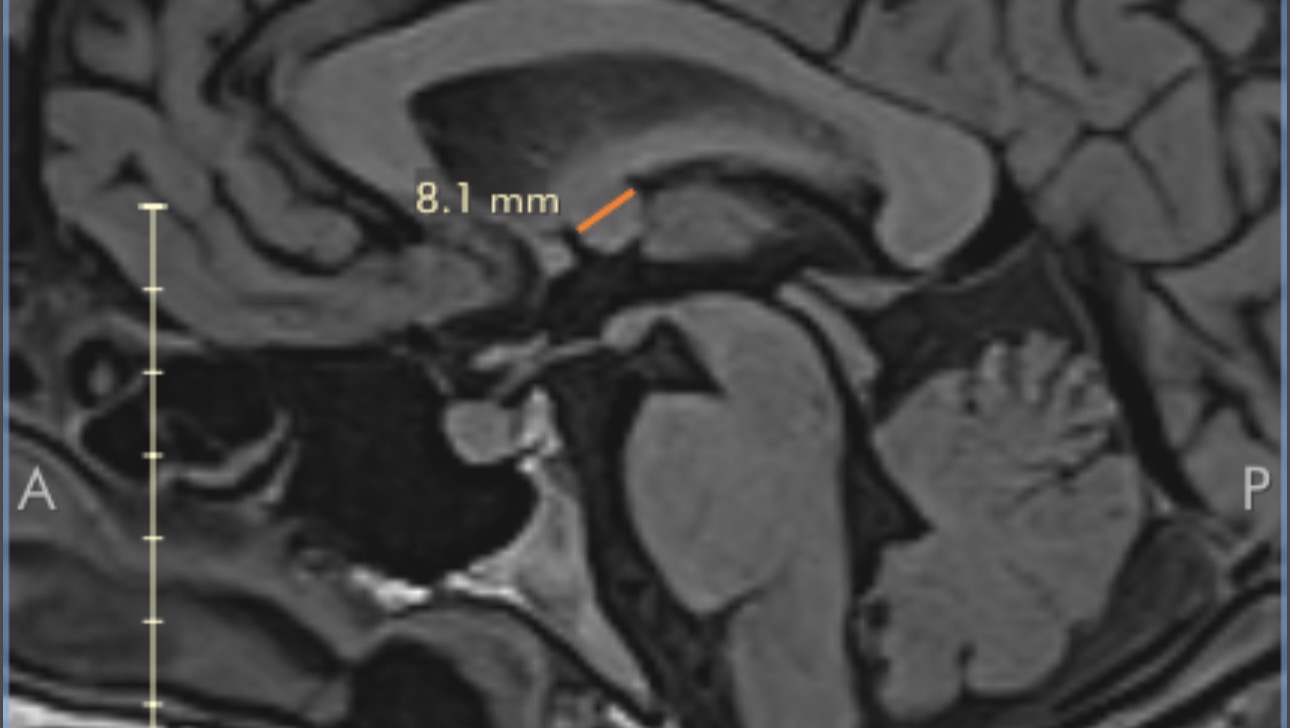

The ED doctor came into my room and squatted down beside me; instantly, I knew something was wrong. "Has anyone told you yet the results?" he asked. I said no... and he continued to tell me that they found an 8.1 mm tumor in the 3rd ventricle of my brain, called a colloid cyst.

A colloid cyst is a benign, slow-growing brain tumor that's filled with a gelatinous material called colloid. It's not cancer. It's thought to form when you are growing in the womb and usually doesn't present issues until your 30s/40s. It's the most rare type of brain tumor and makes up 1% of all brain tumors; 3 in a million people are affected by this type of tumor. It usually doesn't cause people issues until it grows to the point of blocking CSF (cerebral spinal fluid) drainage or starts pressing against structures in your brain.

This is why I have had this headache. Neurosurgery was consulted and after an MRI for better pictures, it was diagnosed as a colloid cyst. The only solution is to have it removed via endoscopic brain surgery.

The team at DHMC didn't seem very concerned because my neuro exams were normal and the only symptom I have is a headache; however, in the same sentence, they told me the worst thing that could happen is sudden death from acute hydrocephalus (build-up of CSF causing brain swelling, loss of consciousness, and subsequently death). I was already so overwhelmed by everything I didn't ask too many questions, but after sitting with this diagnosis for a couple of days and doing a lot of research, the fact that I have a constant headache and the increased headache when I do anything that raises my blood pressure means that the cyst is temporarily blocking the drainage of CSF, building up that pressure, causing the headache to be worse.